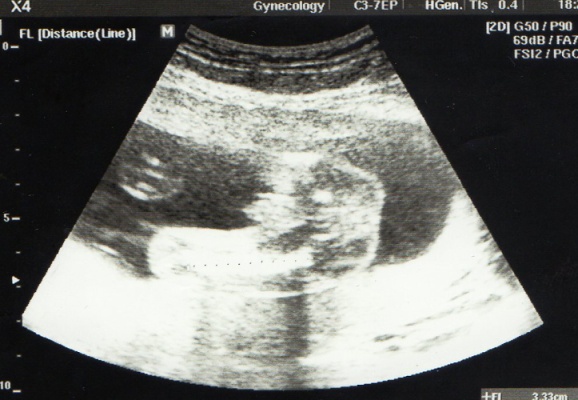

Ahoj,chci se zeptat,poznáte co to je...jestly kluk nebo holka?Chtěla jsem se zeptat DR ale přítel to nechce vědět a pořád tam se mnou chodí...

tuhle fotečku mám z videa ze 4D a je to pohled ze spodu na prdelku a nožičky...předem děkuji všem za snahu

já bych to přirovnala asi k tomuto obrázku,ale fakt se to blbě určuje